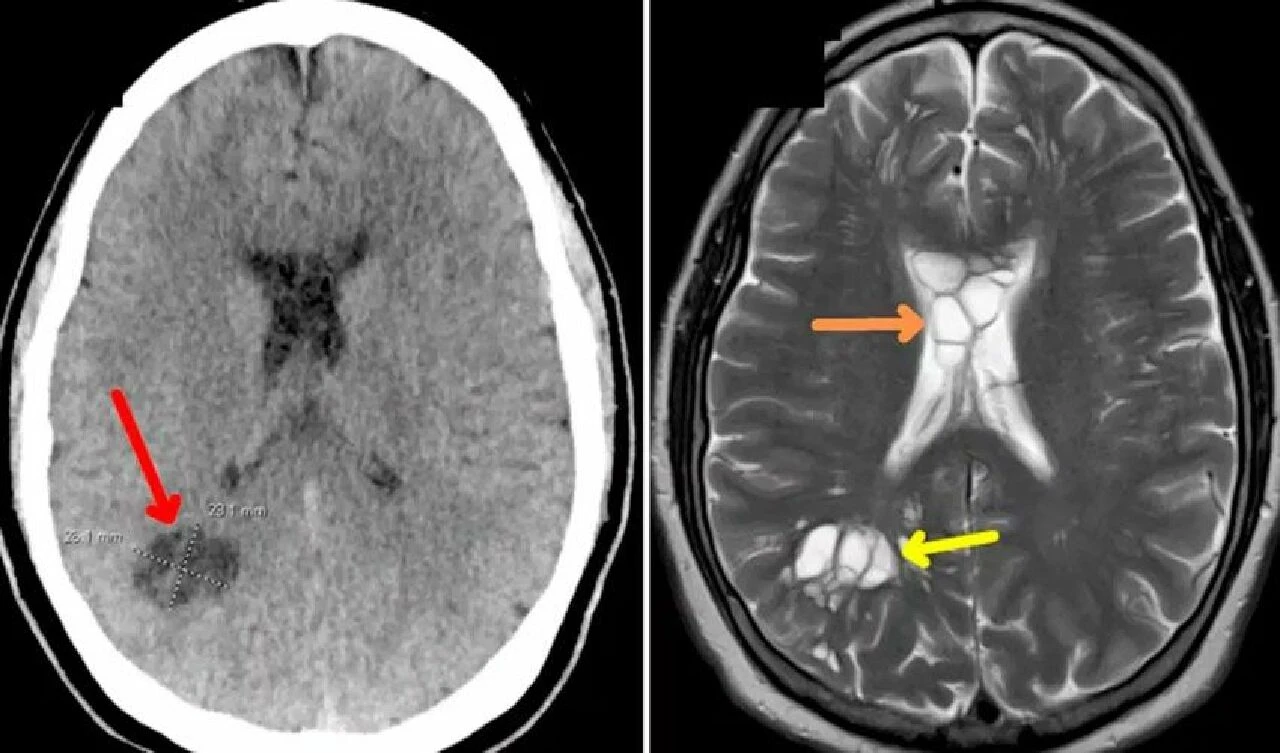

Doktorlar, kistlerin tenya yumurtaları olduğunu, tenyanın ise kafatasının altındaki dokuyu tahriş ettiğini söylediler. Hasta, yemek tercihlerinde az pişmiş eti sevdiğini söylemesiyle tenyanın vücuduna nasıl girdiği de ortaya çıkmış oldu.

Doktorlar, yaptıkları araştırmaların ardından adama nörosistiserkoz tanısını koydular. Bu tanı, tenyanın larva yumurtalarının vücudun çeşitli yerlerinde görülmesinin ardından konuldu. Uzmanlar, tenya parazitinin, hastanın az pişmiş eti yedikten sonra vücuduna girdiğini kan dolaşımı sayesinde beyne doğru ilerlediğini düşünüyorlar. Sağlık görevlileri, "Hastanın hayatı boyunca az pişmiş et tercih etmesi bu duruma yol açmış olabilir" dedi.

Hasta, yoğun bakıma alındı ve beynindeki şişliğin iyileşmesi için iki hafta boyunca tedavi gördü. The Mirror'ın haberine göre, hastayı tedavi eden doktorlar, bu durumdaki hastaların yaklaşık yüzde 80'inde nöbetlerin meydana geldiğini de kaydetti.